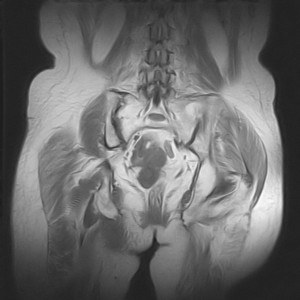

图像太差了 1、右侧臀肌旁脓肿? 建议增强 2、左侧股骨头坏死并半脱位

1、左侧股骨头坏死并髋关节半脱位;

2、右侧臀肌感染,(可能褥疮所致)